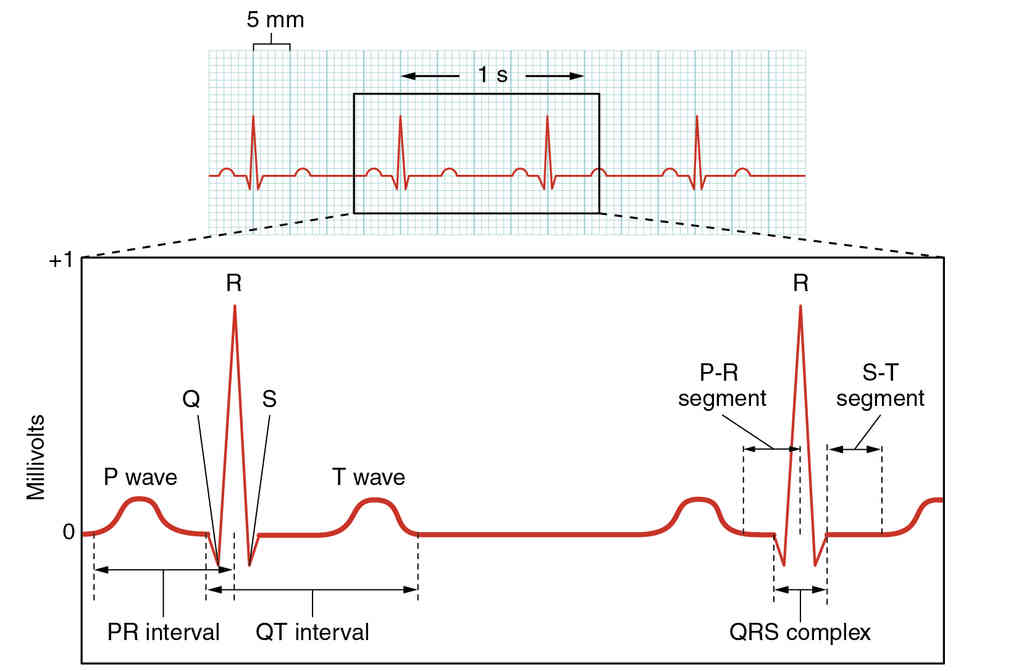

This page is under construction. For now, it is just a resource of the images found in the OpenStax Anatomy and Physiology Handbook. It wil slowly change into a revision tool. Each slide has a number. Use this to refer to the slide. When completed, it will have an unlabelled section, with labelled slides in parallel. On the unlabelled slides, write your answer and use the labelled slide to assess yourself. Keep track by also noting the number on each slide. Improvement at each attempt is important, more so than full marks on a first attempt.